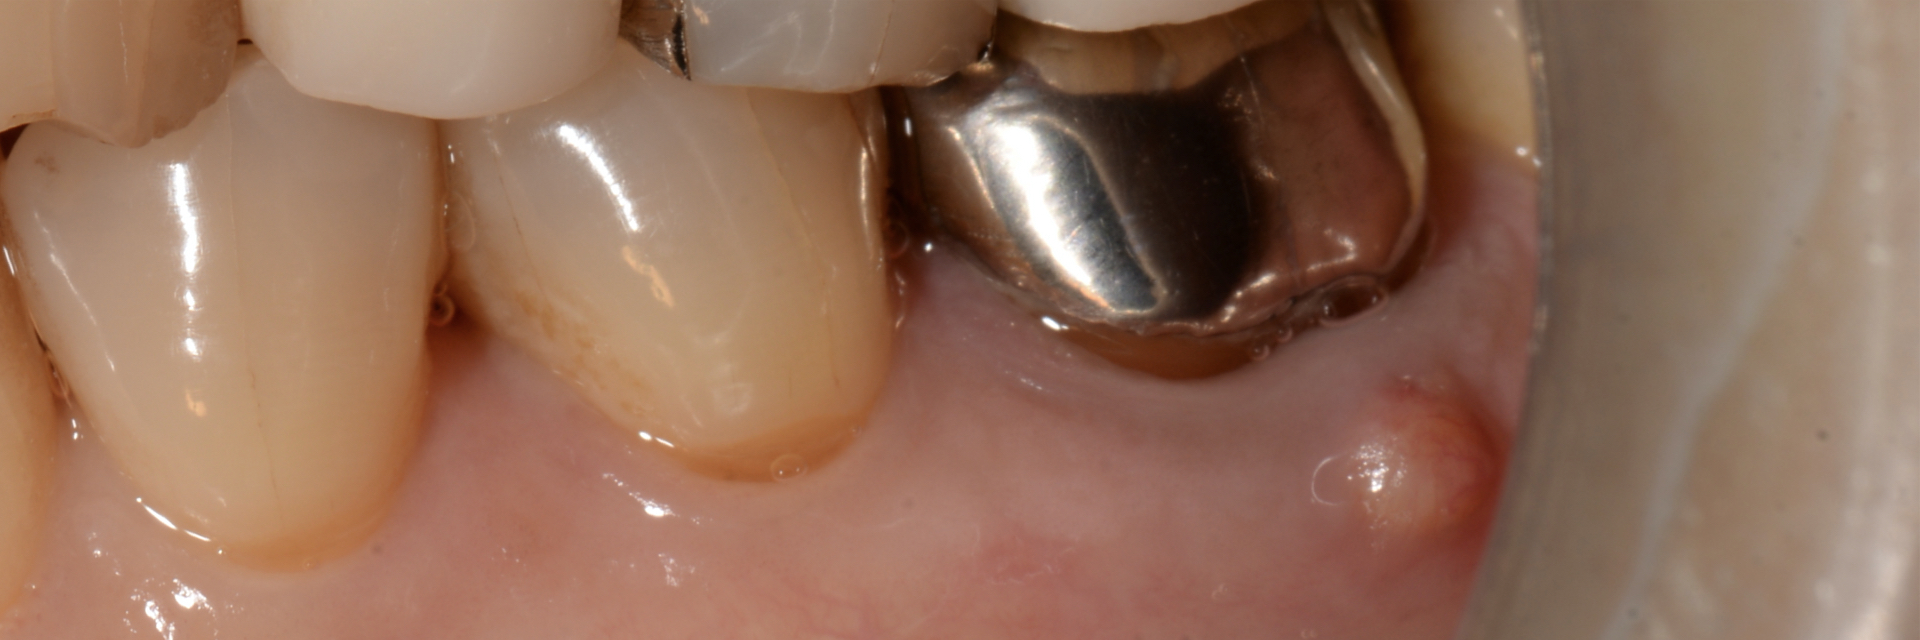

上唇の腫脹を認め、CT検査にて根尖部に嚢胞様透過像を認めた。左上の前歯が不自然に大きく噛み合わせが強くなっていたことがフレアアップの一因と考える。精密根管治療を行い、感染経路を遮断したのち歯根端切除術にて嚢胞を摘出した。

治療前

治療中